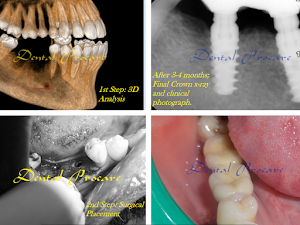

Welcome to our gallery

See how our company transforms ideas into reality. This gallery is a visual testament to our work and achievements.